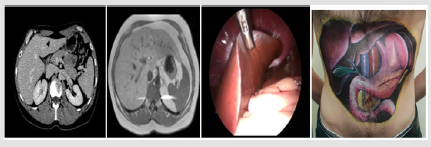

The use of images is mandatory in several methods because it is the foundation on which they are based (CIAP (Clarification, Illustration, Application, Participation)-Mini Talk Chalk) [10]. The other methods use it widely (60% in reading) despite the optional character of this choice. Short term methods (Micro- Mini teaching), for example, use the image because of its PSE and because It fits perfectly in playful teaching methods (via cartoon images for example). Several disciplines are perfectly suited to teaching through images. These are mainly surgery, radiology, dermatology, anatomopathology and anatomy. Indeed, the image is the primary tool in teaching the anatomy of the ‘’ living human’’ via: imagery (Computed tomography scan and/or Magnetic Resonance Imaging), body painting and video capsules of endoscopic surgery (Figure 1). Whatever the method (and the discipline), the choice of a given image depends on the pre-established educational goals in a perfect alignment between objectives, methods and evaluation. It can be a still, sequential or animated image. It can be real, virtual or both (in augmented reality).

Figure 1: Image used in teaching anatomy (example here of the liver) may be radiological (A, B), laparoscopic (C), body painting (D).